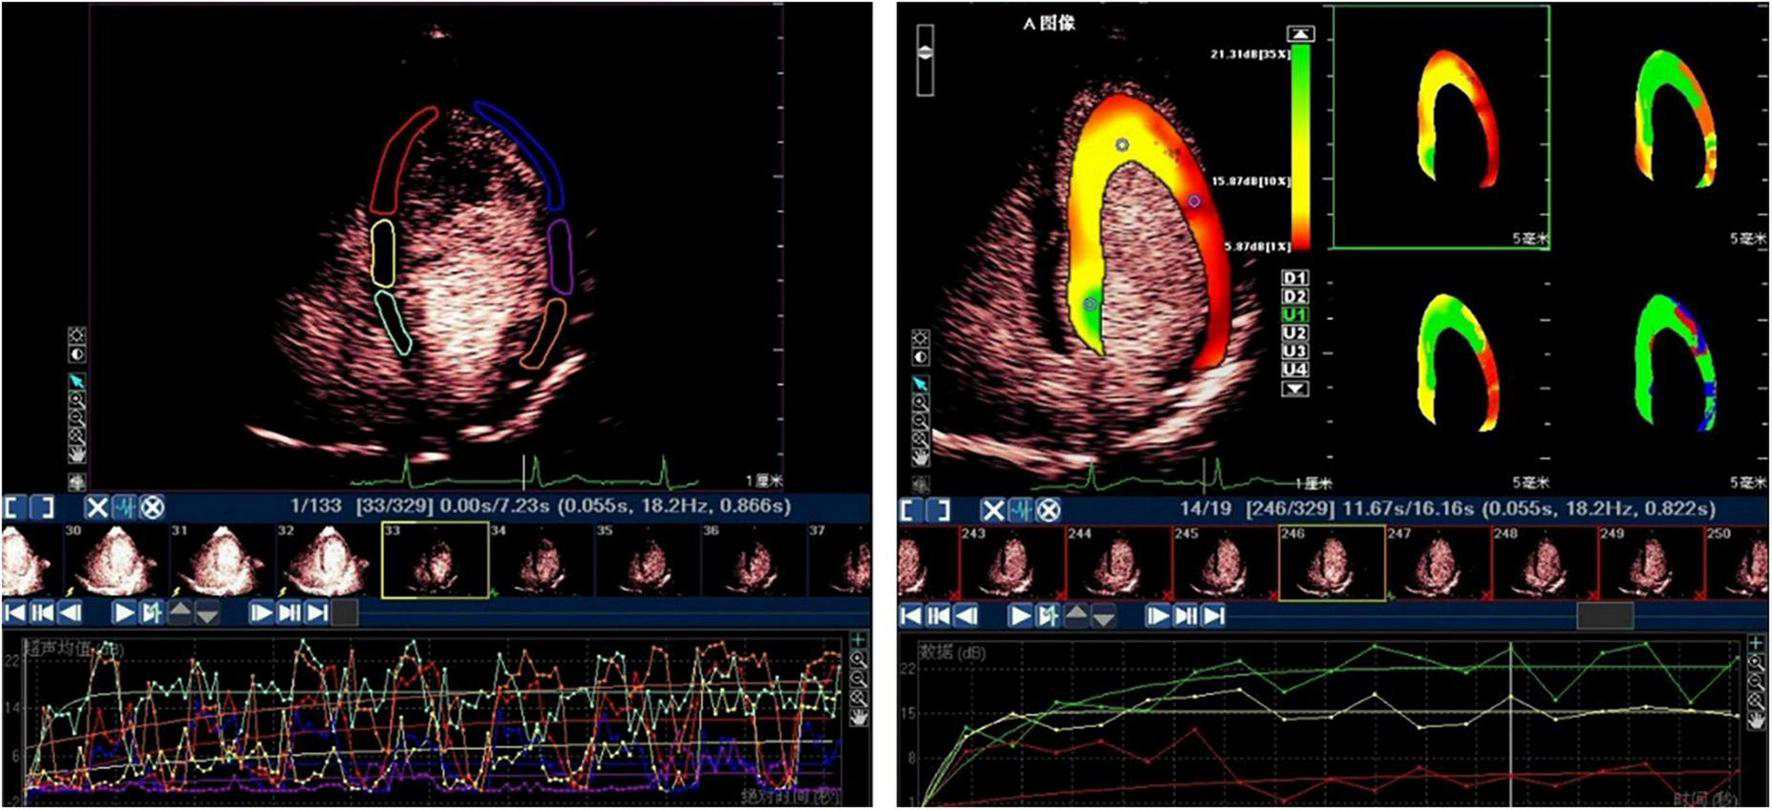

The MCE sequence was transmitted to a personal computer for offline analysis. The quantitative analysis tool in Q-Lab 4.2 software (Philips Medical Systems, Amsterdam, the Netherlands) was used to analyze the images using a random blind method. The data were automatically measured in the region of interest (ROI) and manually positioned using a standard 17-segment LV model. The ROI at the end of each contraction frame after the first flash was automatically copied to all subsequent selected frames. These ROIs were manually realigned frame by frame. According to the functional relationship between indicators, the segmental MCE parameter A was expressed as the average MBV, β represented the average MBF speed, and A × β showed the average MBF (Figure 1) (15–19).

FIGURE 1

The subsequent myocardial refilling curve by ROI method (left) and by parameter display method (right).